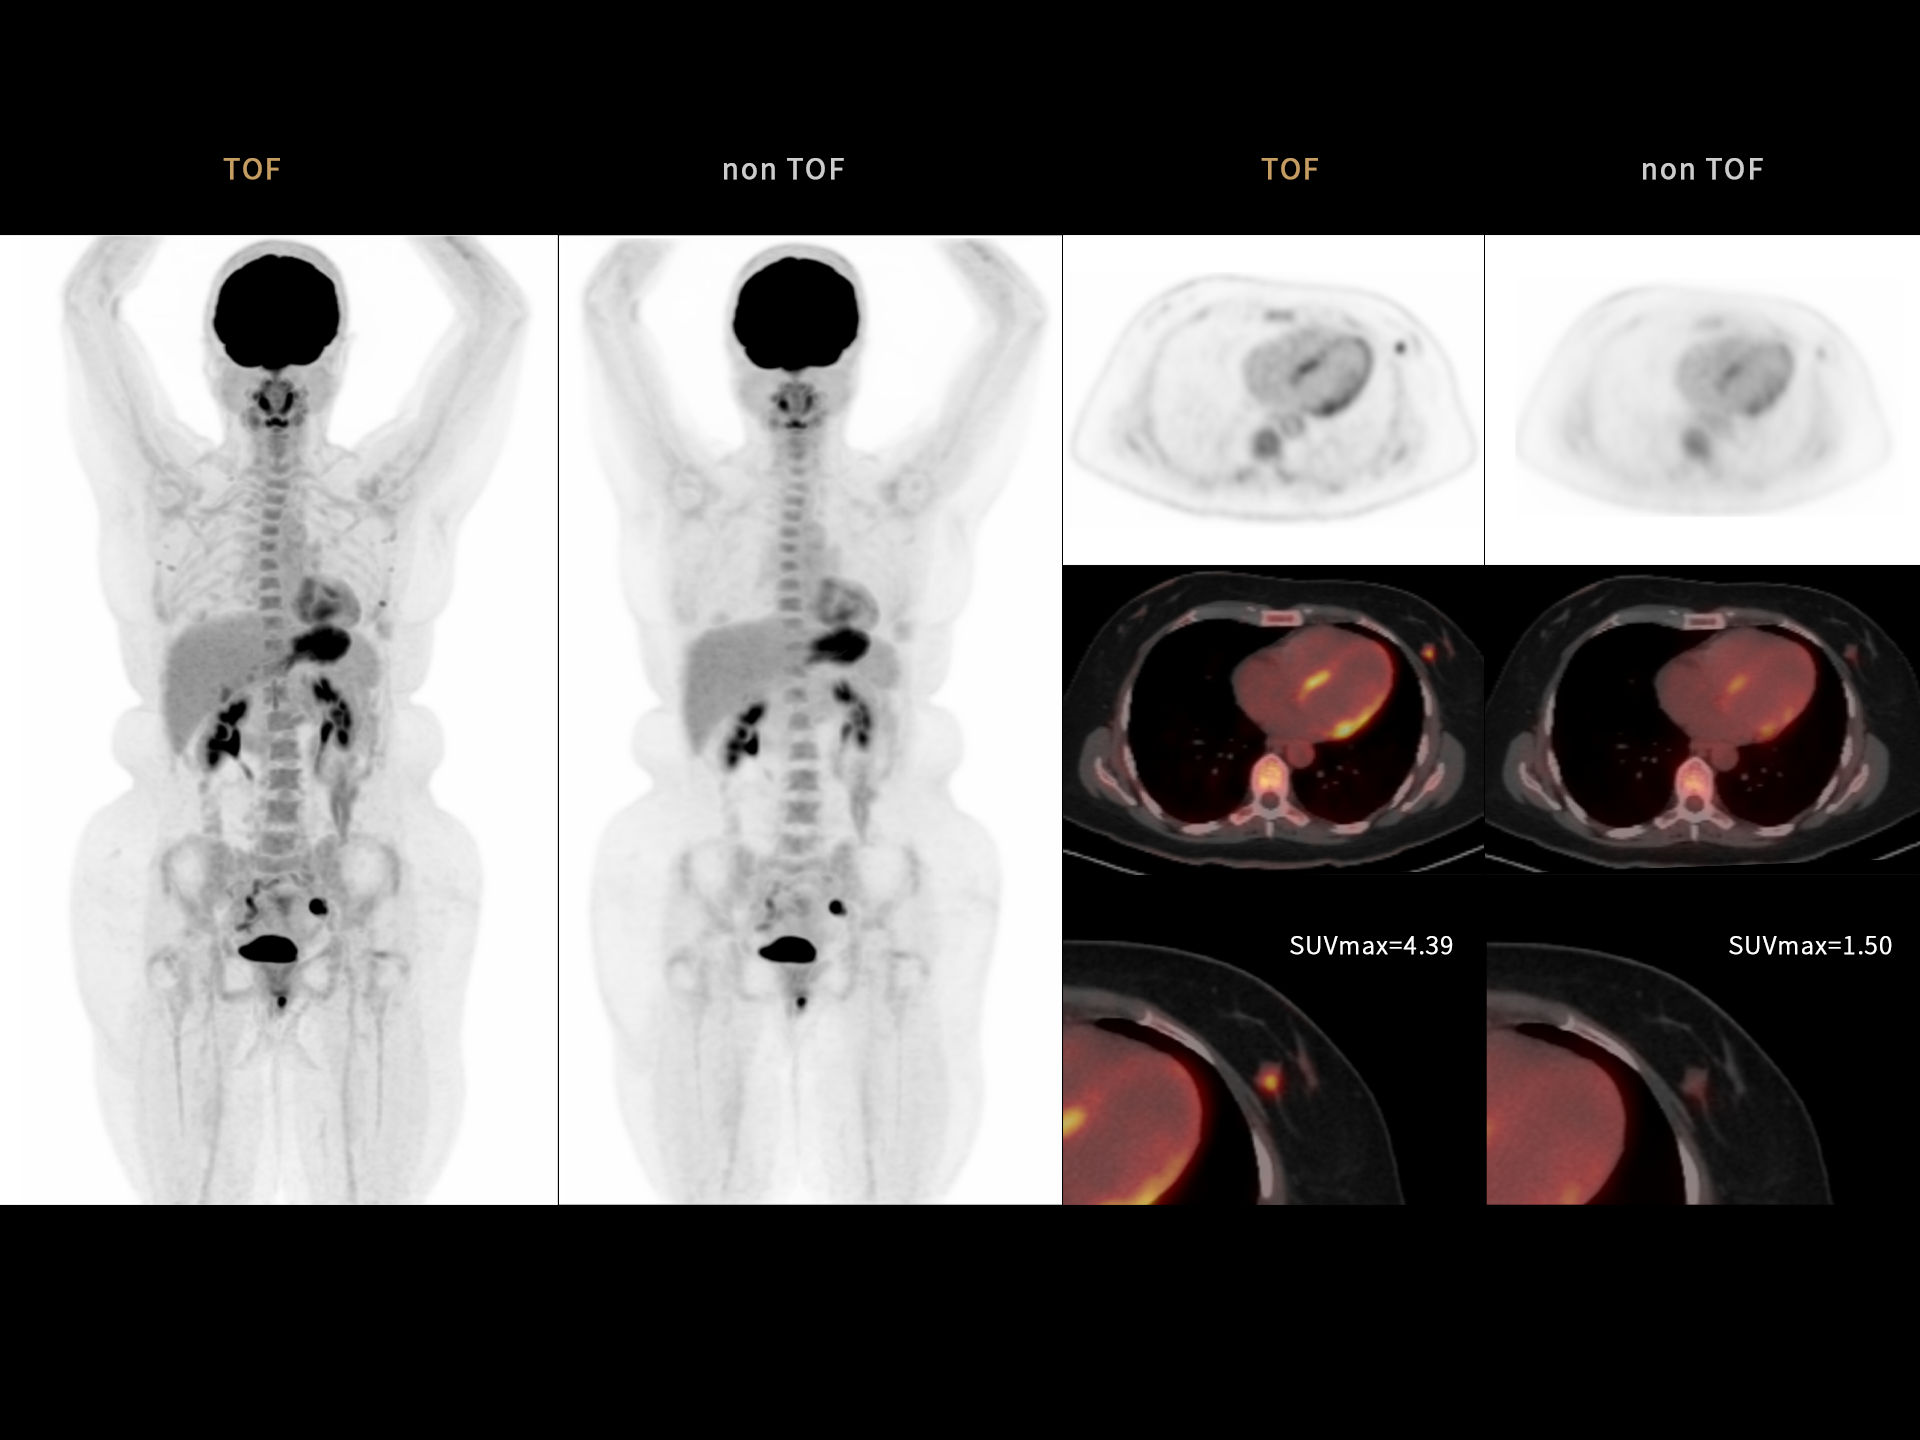

Clarity enhanced by ultra-fast Time of Flight (TOF) resolution of 219 ps enabling better lesion detectability and quantitative accuracy*